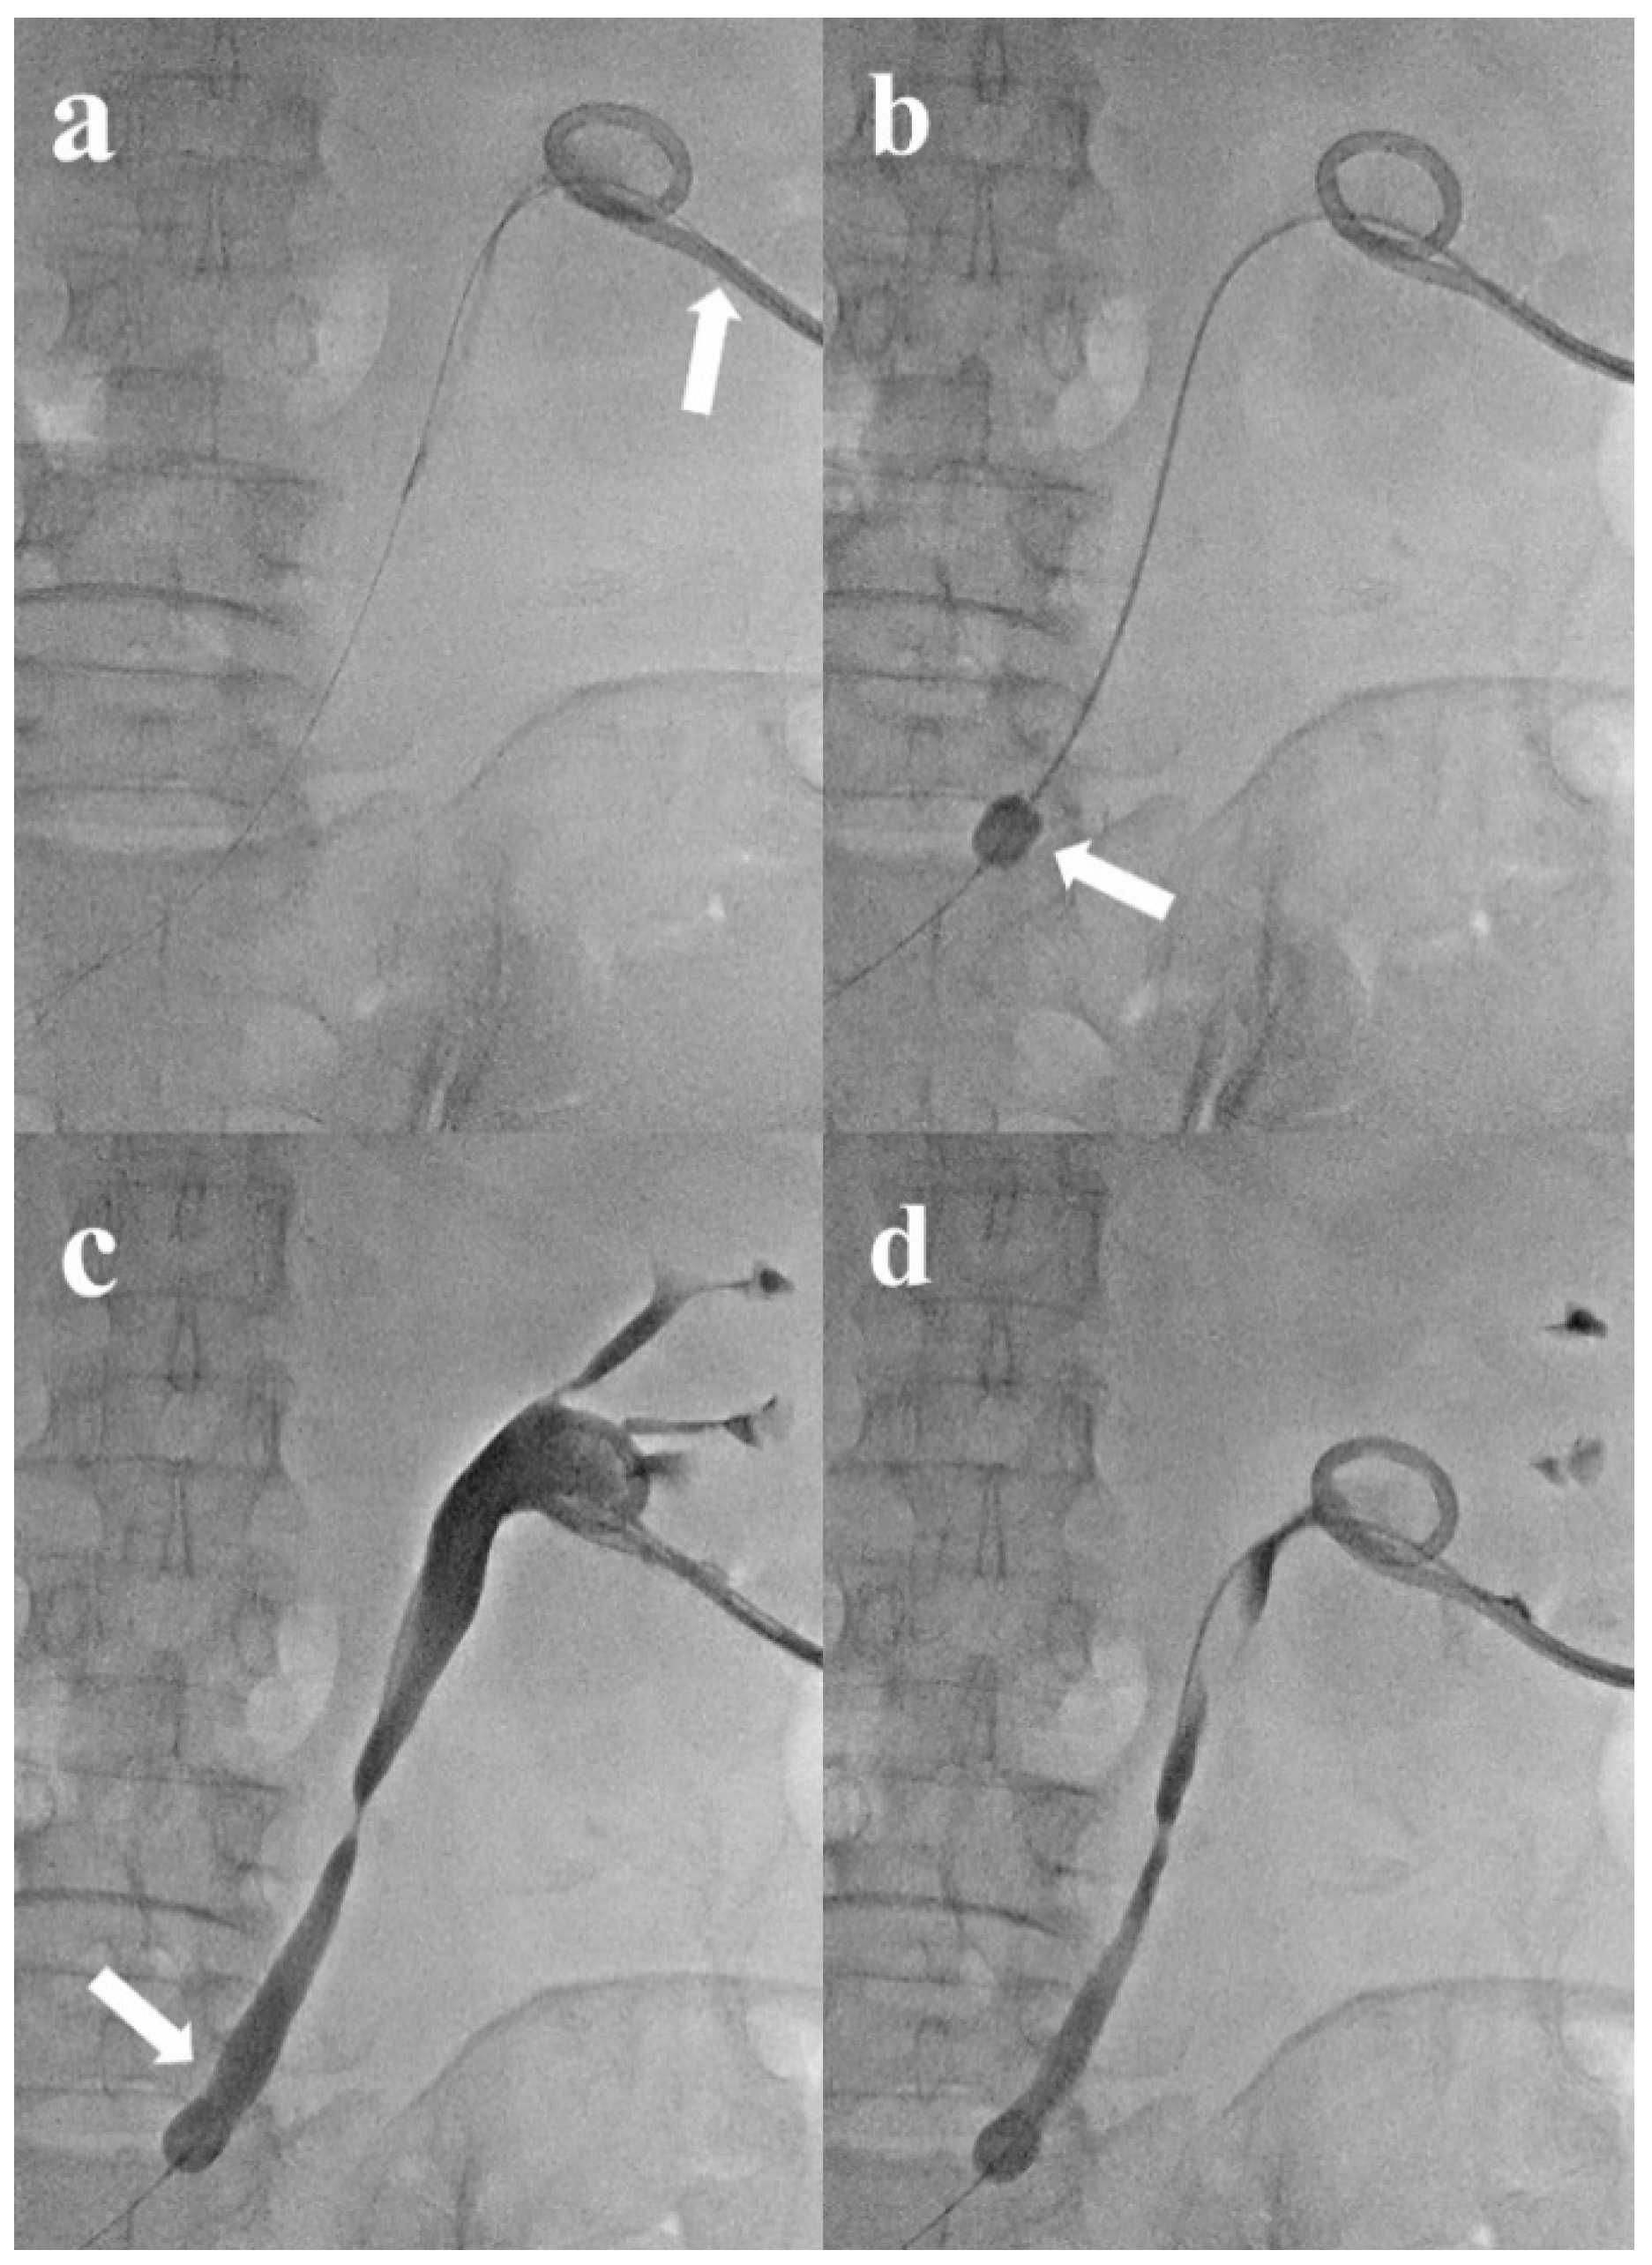

2.2. Temporary Balloon Catheter Indwelling